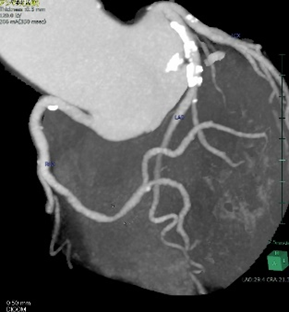

心臓CT検査(下図)は、冠動脈(心臓の栄養血管)の状態をみることができる検査です。3D表示もできることから、回転させながら観察することができます。30分程度の検査ですので、外来で受けることができます。

心臓3D画像心臓3D画像 心臓MIP画像心臓MIP画像